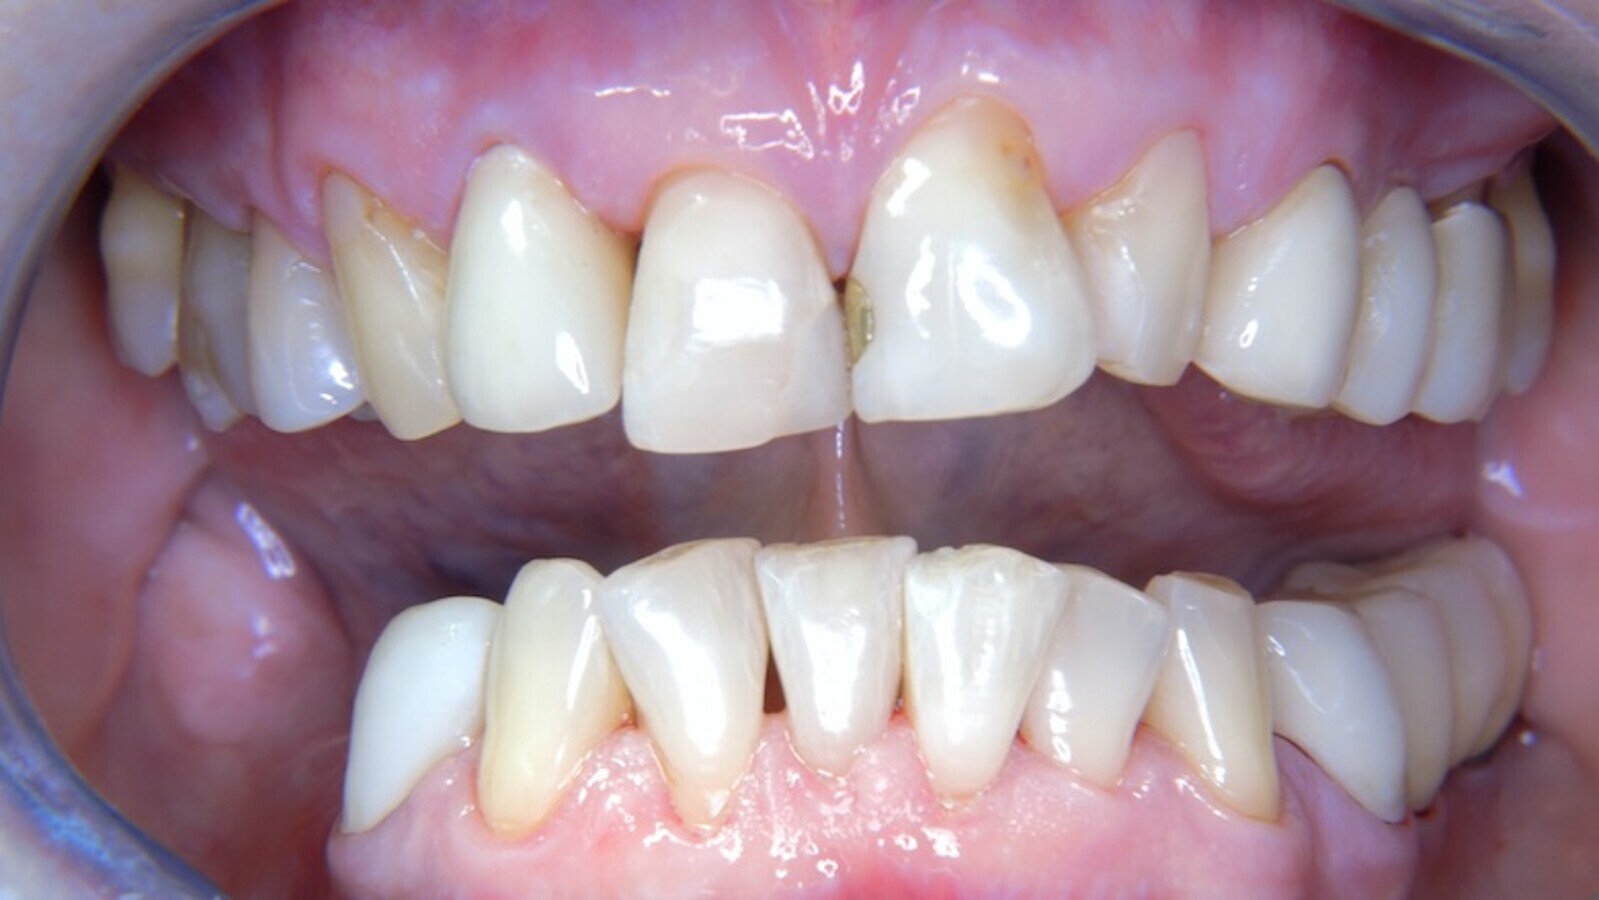

Imagen frontal de la situación de la paciente.

Paciente de 68 años sin enfermedades previas relevantes de salud general que no toma medicación; sus hábitos alimenticios tampoco suponen un riesgo especial. La paciente tiene dos implantes (tercer cuadrante, desde hace cinco años) y enfermedad periodontal previa (periodontitis en etapa IV, grado B) con pérdida dental. Actualmente las condiciones periodontales son estables, pero la periodontitis aumenta de manera determinante las complicaciones biológicas cuando se realizan implantes y puede ocasionar la pérdida de un implante. Para la sesión de profilaxis se hacen cuatro recomendaciones.